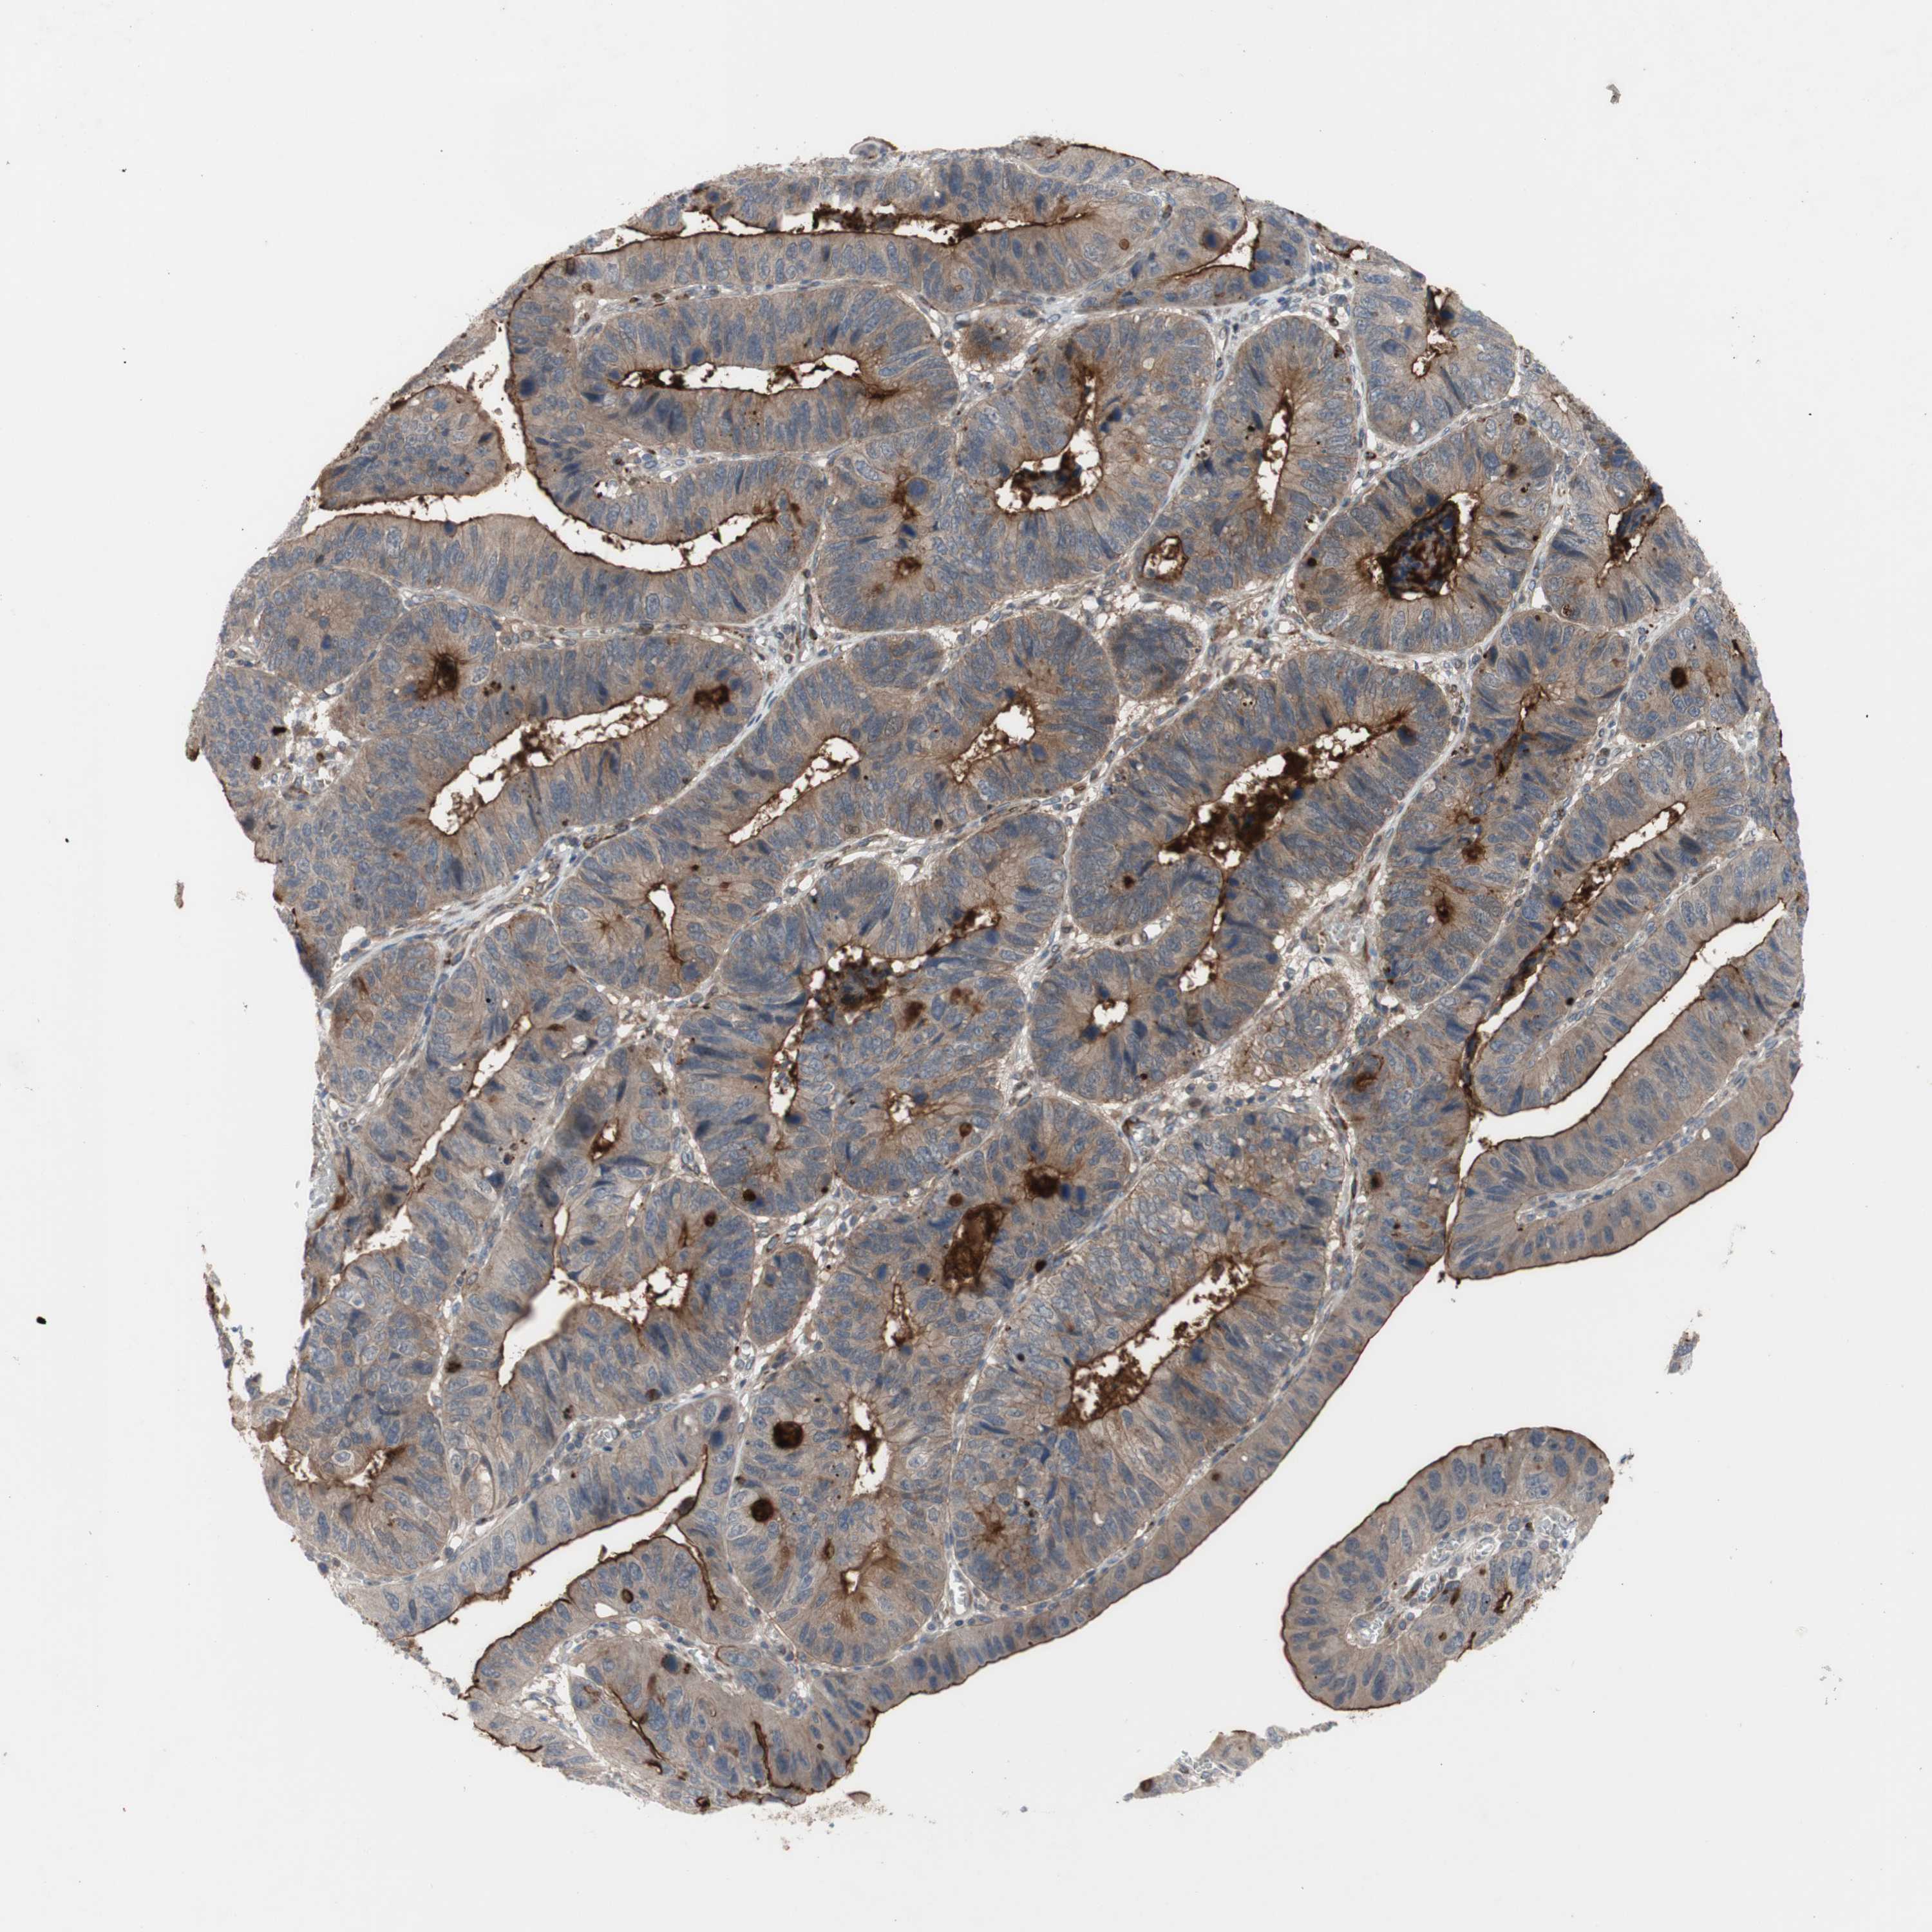

STOMACH CANCER - Protein expressioni

A mouse-over function shows sample information and annotation data. Click on an image to view it in a full screen mode. Samples can be filtered based on level of antibody staining by selecting one or several of the following categories: high, medium, low and not detected. The assay and annotation is described here.

Note that samples used for immunohistochemistry by the Human Protein Atlas do not correspond to samples in the TCGA dataset.

Antibody stainingi

Antibody staining in the annotated cell types in the current human tissue is reported as not detected, low, medium, or high, based on conventional immunohistochemistry profiling in selected tissues. This score is based on the combination of the staining intensity and fraction of stained cells.

Each image is clickable and will lead to virtual microscopy that enables deeper exploration of all samples and also displays staining intensity scores, fraction scores and subcellular localization as well as patient and tissue information for each sample.

Antibody HPA009291

Staining

High

Medium

Low

Not detected

Intensity

Strong

Moderate

Weak

Negative

Quantity

>75%

75%-25%

<25%

None

Location

Nuclear

Cytoplasmic/membranous

Cytoplasmic/membranous,nuclear

Adenocarcinoma, NOS